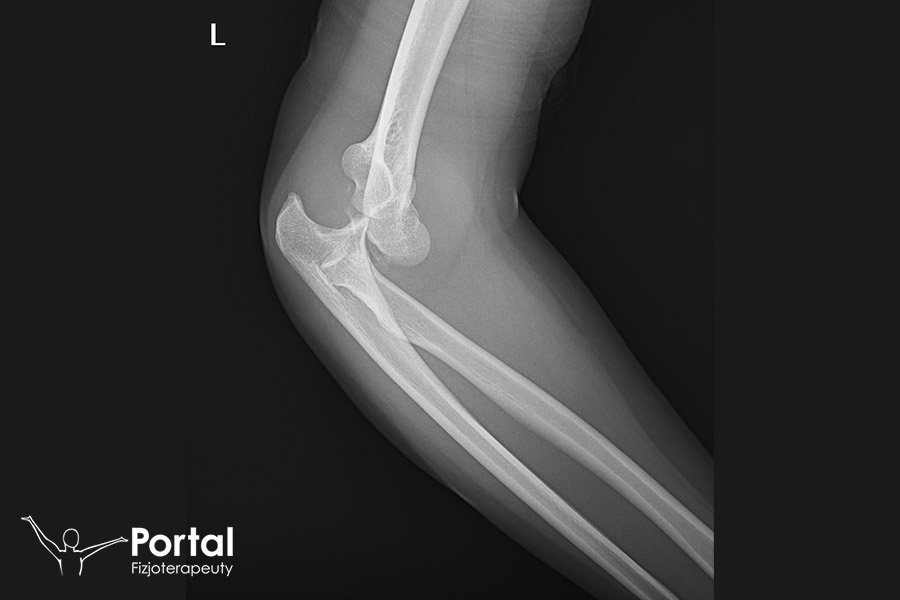

Ryc.1. Zdjęcie RTG jednego z pacjentów naszego Centrum Fizjoterapeuty po zwichnięciu stawu łokciowego.

Repozycja stawu

Repozycja stawu to zabieg ortopedyczny, wykonywany w znieczuleniu miejscowym lub znieczuleniu ogólnym. Może mieć formę zachowawczą lub operacyjną, a jego